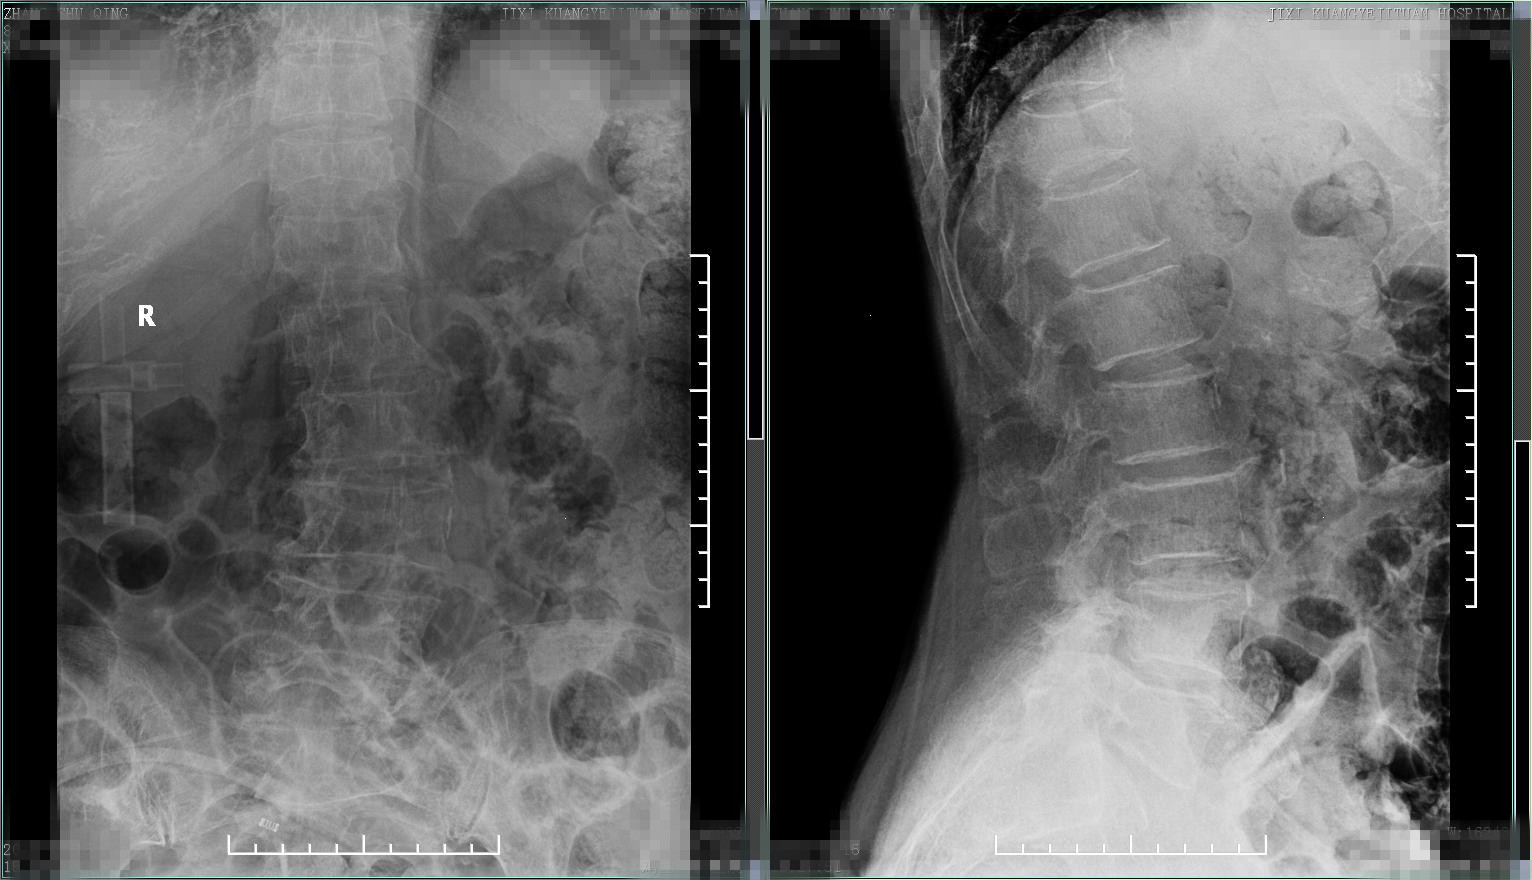

患者2,患者老年女性,80岁,慢性腰背部疼痛多年,程度轻,对日常生活无明显影响,平时可生活自理。就诊前2个月开始腰背部疼痛加重,偶尔夜间能疼痛,口服止痛药物疼痛可减轻,自认为腰椎间盘突出、骨质增生所致,采取针灸治疗半月余,无任何改善,又前往个体中医门诊外敷膏药治疗,疼痛进行加重,并出现因疼痛严重导致翻身困难,于就诊前一周开始出现双下肢麻木、双腿活动不灵活、无力,无法下床站立、行走,逐渐出现大小便*禁失**,就诊时已进展为双下肢截瘫。查腰椎X线片,可见脊柱侧弯、骨质疏松、椎体前缘由变扁。病人出现脊髓损害,进一步查核磁,结果如下: